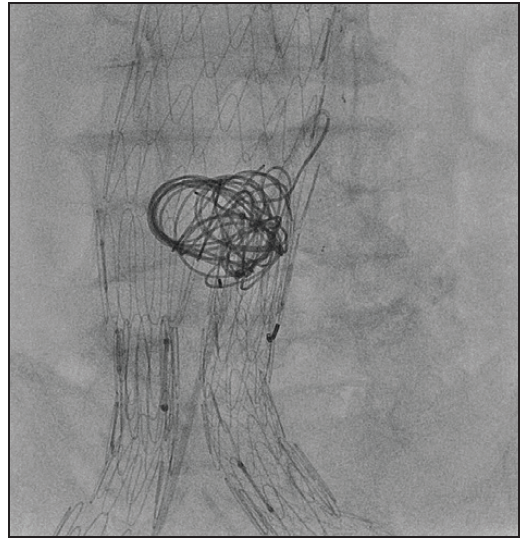

What Are Ruby Coils Made Of . The ruby® coil, pod® (penumbra occlusion device), and packing coil—all. The ruby coils were easily delivered through the microcatheter at a 180° angle. Although each of these products was designed for dedicated purposes, they can be used to complement each other ( figure 1 ). Indicated for arterial and venous. Penumbra’s embolization platform is made up of three unique detachable coil technologies:

The ruby coils were easily delivered through the microcatheter at a 180° angle. Penumbra’s embolization platform is made up of three unique detachable coil technologies: The ruby® coil, pod® (penumbra occlusion device), and packing coil—all. Indicated for arterial and venous. Although each of these products was designed for dedicated purposes, they can be used to complement each other ( figure 1 ).